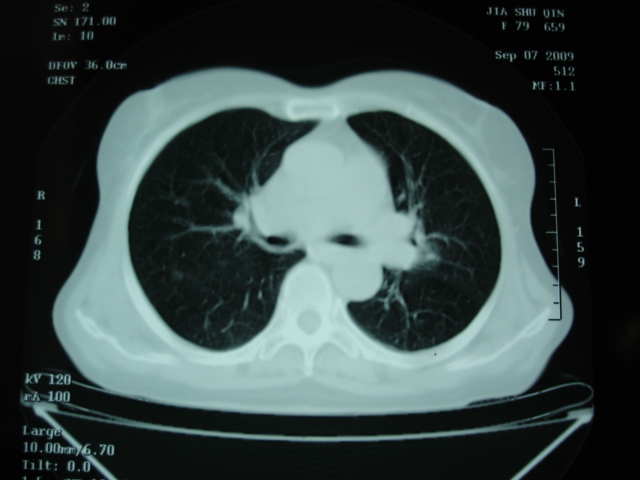

以下是引用卜一在2009-9-7 19:51:00的发言:[br][br] 1 左侧胸内甲状腺占位-多考虑甲状腺腺瘤! 2、左肺门占位-建议增强扫描以便明确性质。 3 慢支并感染! [br]

以下是引用shibing在2009-9-7 20:40:00的发言:[br]左侧胸内甲状腺占位-多考虑甲状腺腺瘤! 2、左肺门占位-建议增强扫描以便明确性质。 3 慢支并感染! [br]